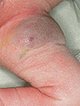

Boy with congenital, blue-livid discolored tumor in the left groin and proximal thigh (photograph from day 3 of life).